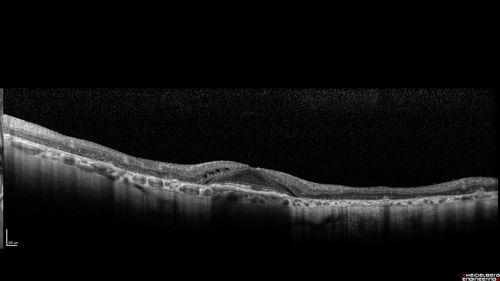

Concentric Geographic Atrophy - 76 year old man

Gradual vision loss, worse at night. VA 20/40 OU.

Concentric Geographic Atrophy - 76 YO male